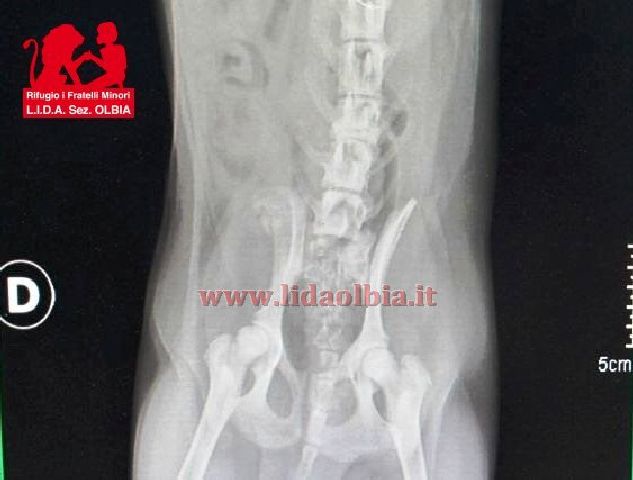

Soccorsa e portata immediatamente al nostro rifugio. Sottoposta a radiografie che hanno evidenziato una paraparesi posteriore con riflessi a destra e sinistra debolissimi o assenti. Frattura terminale della 5 vertebra lombare.

La piccola è giovanissima, avrà circa sei mesi dovrà essere sottoposta ad intervento chirurgico per riallineamento della colonna. Il midollo non dovrebbe aver subito lesioni.